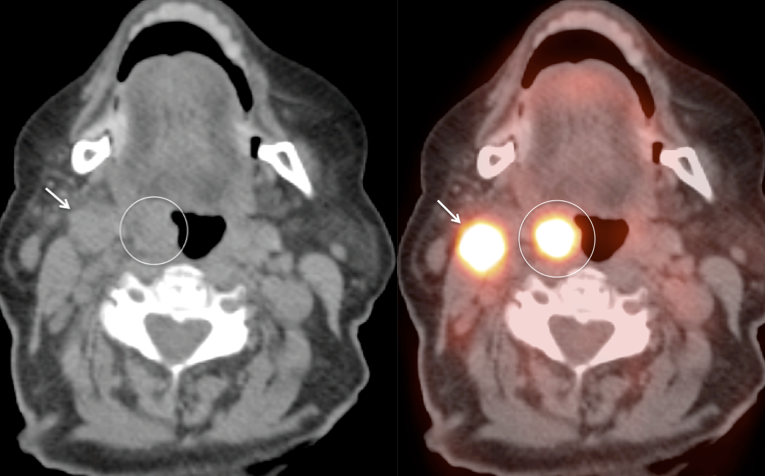

Unilateral FDG-Avid Tonsil (or Relative Increased Avidity of One Tonsil):

Special care is required when assessing the incidental finding of a unilateral hot tonsil (or relative increased uptake within one tonsil) — even though most unilateral hot tonsils are benign. Proposed techniques for assessment have included SUV threshold cutoff values, metabolic tumor volume assessment, and SUV ratios.

Unfortunately, it is advisable to raise at least a degree of concern for most FDG-avid unilateral tonsillar findings. The level of suspicion, of course, depends on the presentation.

At PETCTMD, we utilize the following practical approach for the incidental finding of a unilaterally FDG-avid tonsil:

- Any Unilateral Tonsillar Uptake Associated with Hypermetabolic Cervical Nodes:

Clearly, the presence of hypermetabolic cervical nodes dramatically increases the likelihood of malignancy (and the confidence of your reporting).